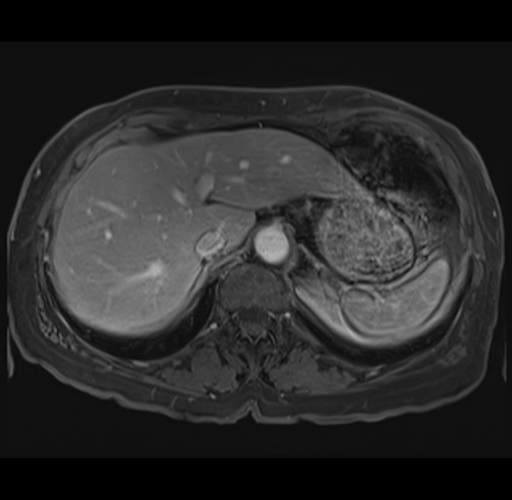

MRI T1

Imaging analysis

Based on your CT findings, which issue(s) would give reason for "planned slowing down moment(s)" in this case?

Considering a standard right hepatectomy procedure, what step(s) of the operation would you do differently in this case?